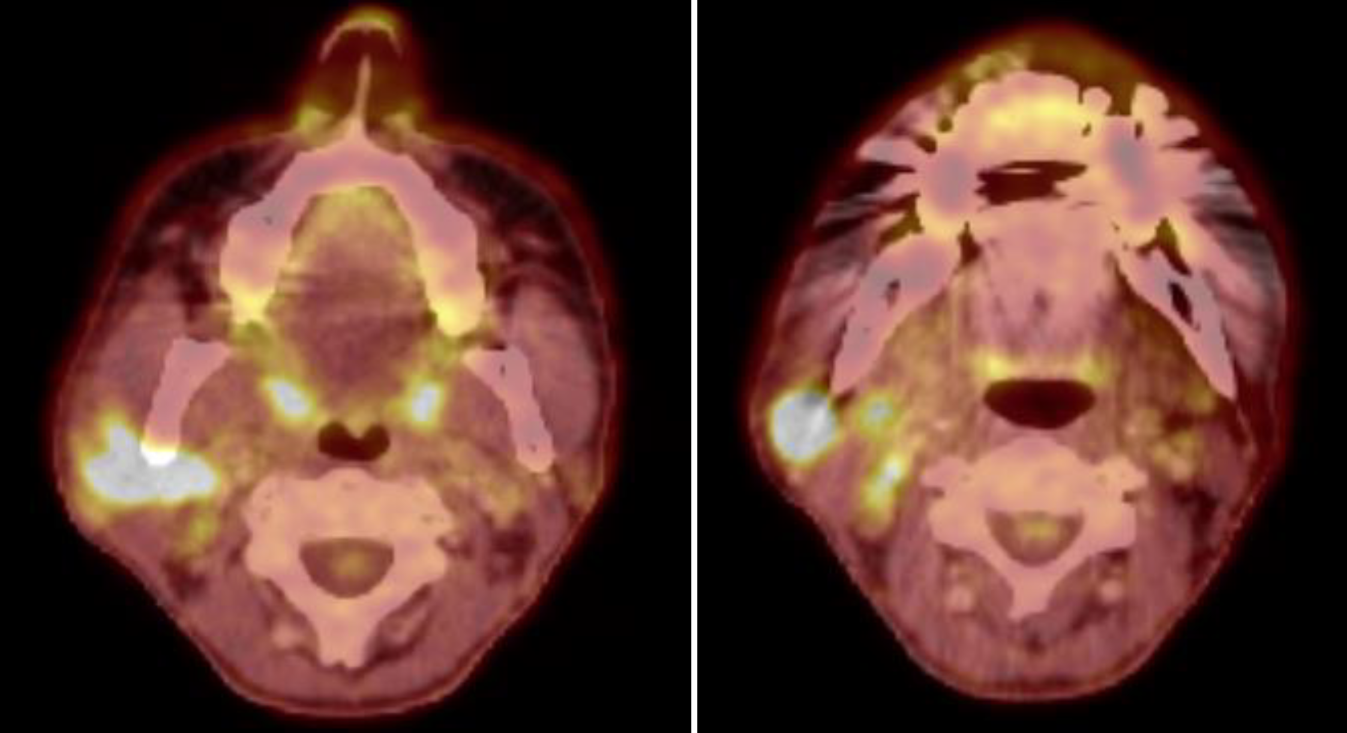

18-Fluordesoxyglucose-Positronenemissionstomographie-Fusions-Computertomographie (18-FDG-PET-Fusions-CT) und Ganzkörper-18-FDG-PET vom Juni 2023 zeigen den Primärtumor und die Hals-Lymphknotenmetastasen, jedoch keine Fernmetastasierung (Abb. 1 und 2).

Abb. 1

18-FDG-PET-Fusions-CT vom Juni 2023